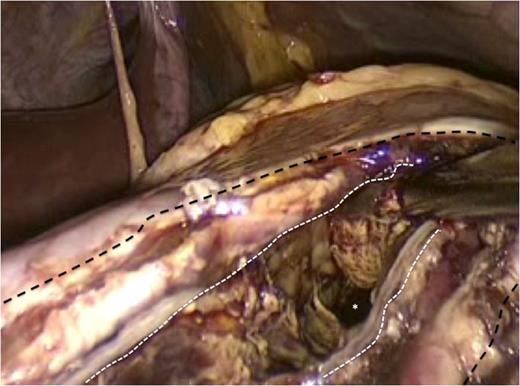

The gastric lumen was entered through the incision at the anterior stomach wall (margins indicated by white arrows). Conventional straight laparoscopic instrument can be seen developing an tunnel at the posterior stomach wall at the area where bulging from the pseudocyst is most prominent.

For this case, we used conventional 35 mm straight instruments, a rigid 30o laparoscope and no access platforms. This made the procedure technically difficult with considerable instrument ‘sword-fighting’ and limited ‘tunnel-vision’ as evident in Fig. 4. However, we used previously described techniques for SILS to complete this operation. The ‘hanging manoeuvre’ [7] was quite useful in this operation and allowed us to compensate for the absence of instrument triangulation that is inherent with the performance of SILS. We have used the ‘hanging manoeuvre’ liberally in our SILS experience [7]. It is a simple, cheap and effective manoeuvre and should be in the armamentarium of surgeons performing SILS operations.